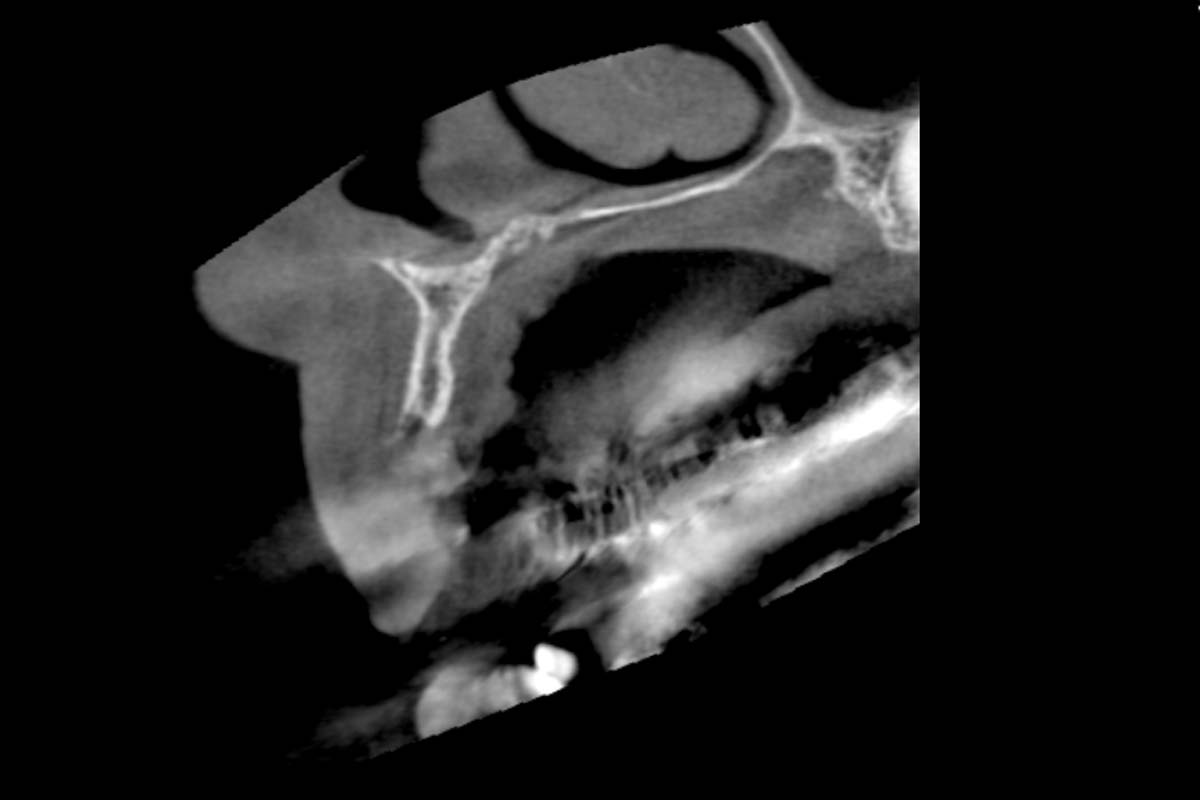

Initial clinical situation: Bone defect in the upper right maxilla (teeth #14-16)